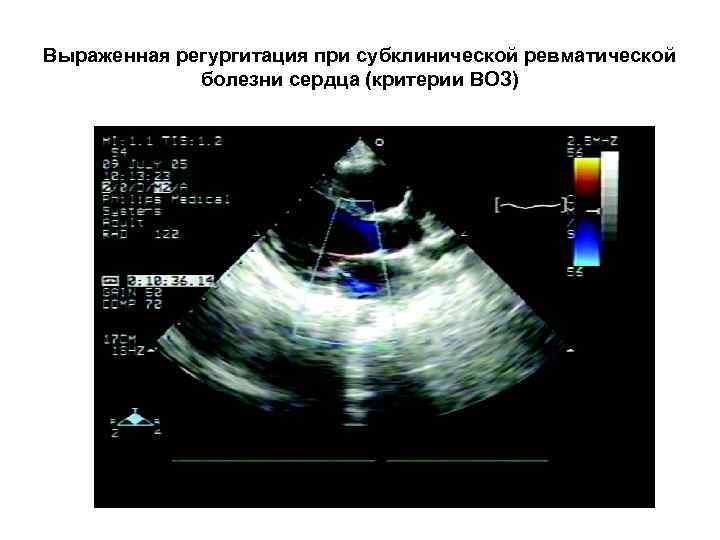

Эхо. КГ при субклинической ревматической болезни сердца

Выраженная регургитация при субклинической ревматической болезни сердца (критерии ВОЗ)

Эхо. КГ критерии субклинического ревматического поражения сердца Допплерографические (критерии ВОЗ 2001): • Поток регургитации > 1 см длиной • Поток регургитации как минимум в двух проекциях • Мозаичный цветной поток с пиковой скоростью >2, 5 м/с • Поток сохраняется на протяжении всей систолы (митральный клапан) или диастолы (аортальный клапан) Комбинированные пересмотренные критерии: Допплерографические признаки: • Регургитация любой степени, видимая как минимум в 2 проекциях + минимум 2 из морфологических признаков: • Подтягивание створок • Утолщение подклапанных структур • Утолщение створок клапана